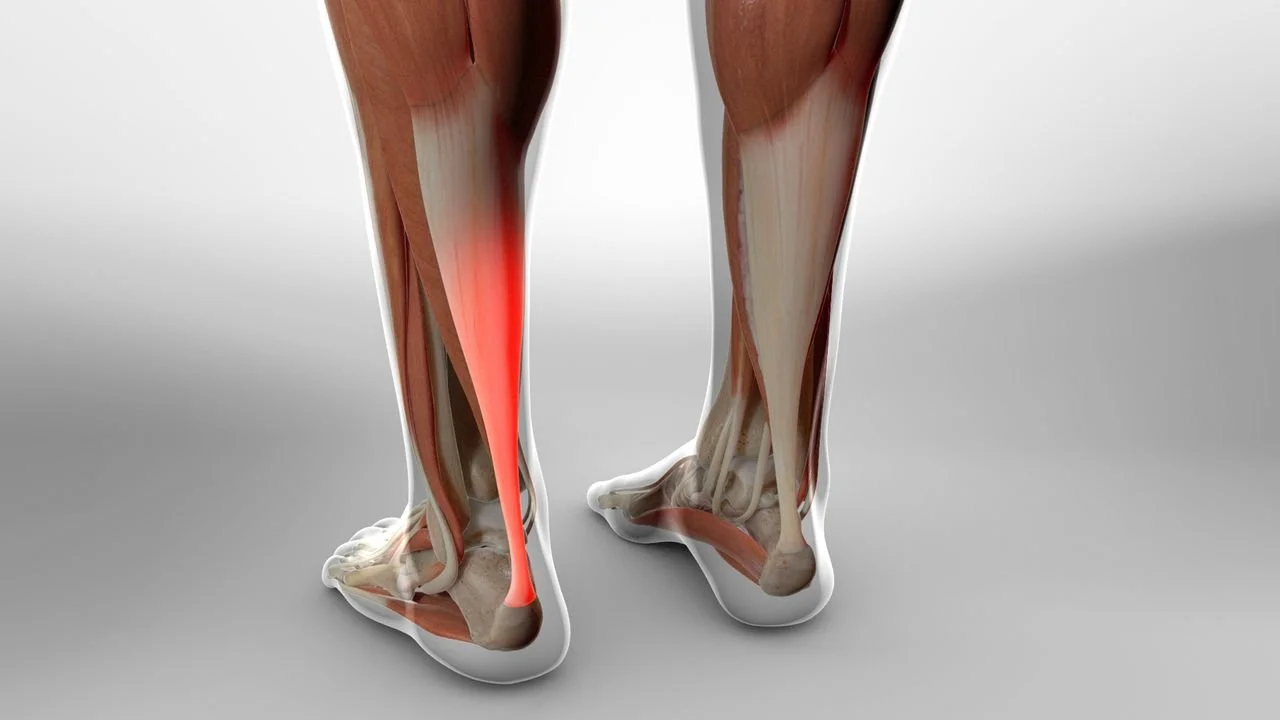

We strive to restore your foot & ankle function using the the least invasive treatment possible so you can get back to on your feet. Dr. Henry uses both nonoperative treatments and surgeries to get you back to doing what you love. These are just some of the procedures Dr. Henry specializes in.

Through a joint decision-making process, we may recommend surgical treatment if we believe the potential benefits outweigh the risks. For patients with chronic (long-term) conditions, the decision for surgery may come after a period of nonoperative treatment, including shoewear changes, orthotics (shoe inserts), ankle/foot braces, physical therapy, medication, activity optimization, and injections. You will discuss this in your consultation with Dr. Henry.